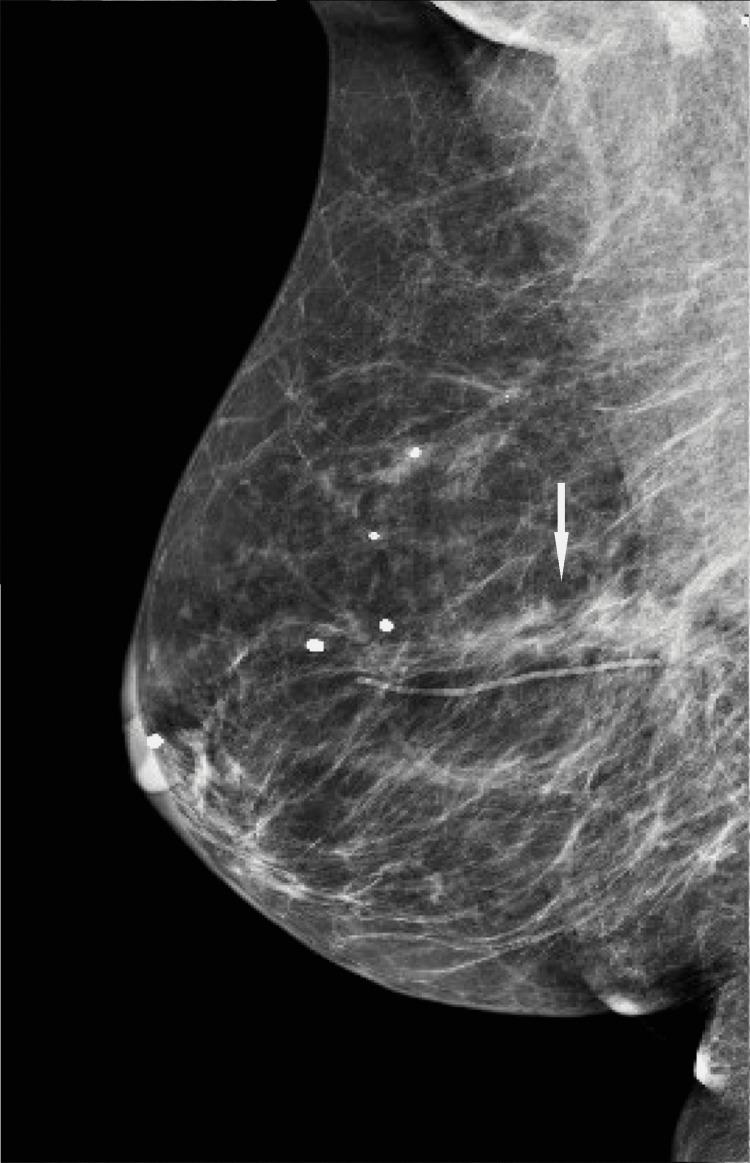

We describe a case of pathology-proven invasive lobular breast cancer (ILC) arising in a scar over 15 years after lumpectomy for previous invasive ductal carcinoma (IDC). The tumor was detected on screening mammography as a new focal asymmetry at the scar site and confirmed at diagnostic mammography. Ultrasound demonstrated an irregular, shadowing, hypoechoic mass at the scar site. Ultrasound-guided biopsy revealed poorly differentiated invasive lobular carcinoma. MRI and CT showed an irregular mass with pectoralis muscle invasion. Multimodality imaging findings are described. This is the first case to our knowledge reporting multimodality imaging findings of a breast cancer developing at the site of a surgical scar that is histologically different from the originally resected cancer.

我们描述了一例经病理证实的浸润性小叶乳腺癌(ILC)病例,该病例发生于先前因浸润性导管癌(IDC)行肿块切除术后15年以上的瘢痕处。肿瘤在筛查乳腺X线摄影中被检测为瘢痕部位新出现的局灶性不对称,并在诊断性乳腺X线摄影中得到证实。超声显示瘢痕部位有一个不规则、有阴影、低回声肿块。超声引导下活检显示为低分化浸润性小叶癌。MRI和CT显示有一个不规则肿块,侵犯胸大肌。描述了多模态成像结果。据我们所知,这是首例报告手术瘢痕部位发生的组织学上与最初切除的癌症不同的乳腺癌的多模态成像结果的病例。